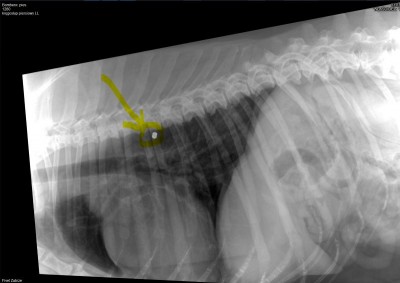

Niestety to nie koniec jego ortopedycznych problemów. W badaniu fizykalnym Pan doktor stwierdził zwiększoną bolesność odcinka lędźwiowo-szyjnego kręgosłupa. Na RTG kręgosłupa ma widoczne zmiany typowe dla zaawansowanej postaci zespołu końskiego ogona, zaawansowaną spondylazę a na domiar złego przewężenia w przestrzeniach międzykręgowych m.in. w odcinku szyjnym co ma wpływ na jego czucie (kwestie neurologiczne) i stanowi ryzyko paraliżu w przyszłości :(

Zaskoczeniem był dla nas śrut, który jest bardzo blisko kręgosłupa szyjnego. Tak – ktoś do niego strzelał :(

W związku z jego ogólnym stanem Pan doktor jest zdania, że lepiej go teraz nie ruszać, bo zapewne tkwi tam od dawna a przy zabiegu może dojść do naruszenia kręgosłupa i niepełnosprawności :/

Kręgosłup szyjny 1.jpg

Plik ściągnięto 10 raz(y) 24.56 KB

Kręgosłup piersiowy śrut 1.jpg

Plik ściągnięto 10 raz(y) 42.33 KB